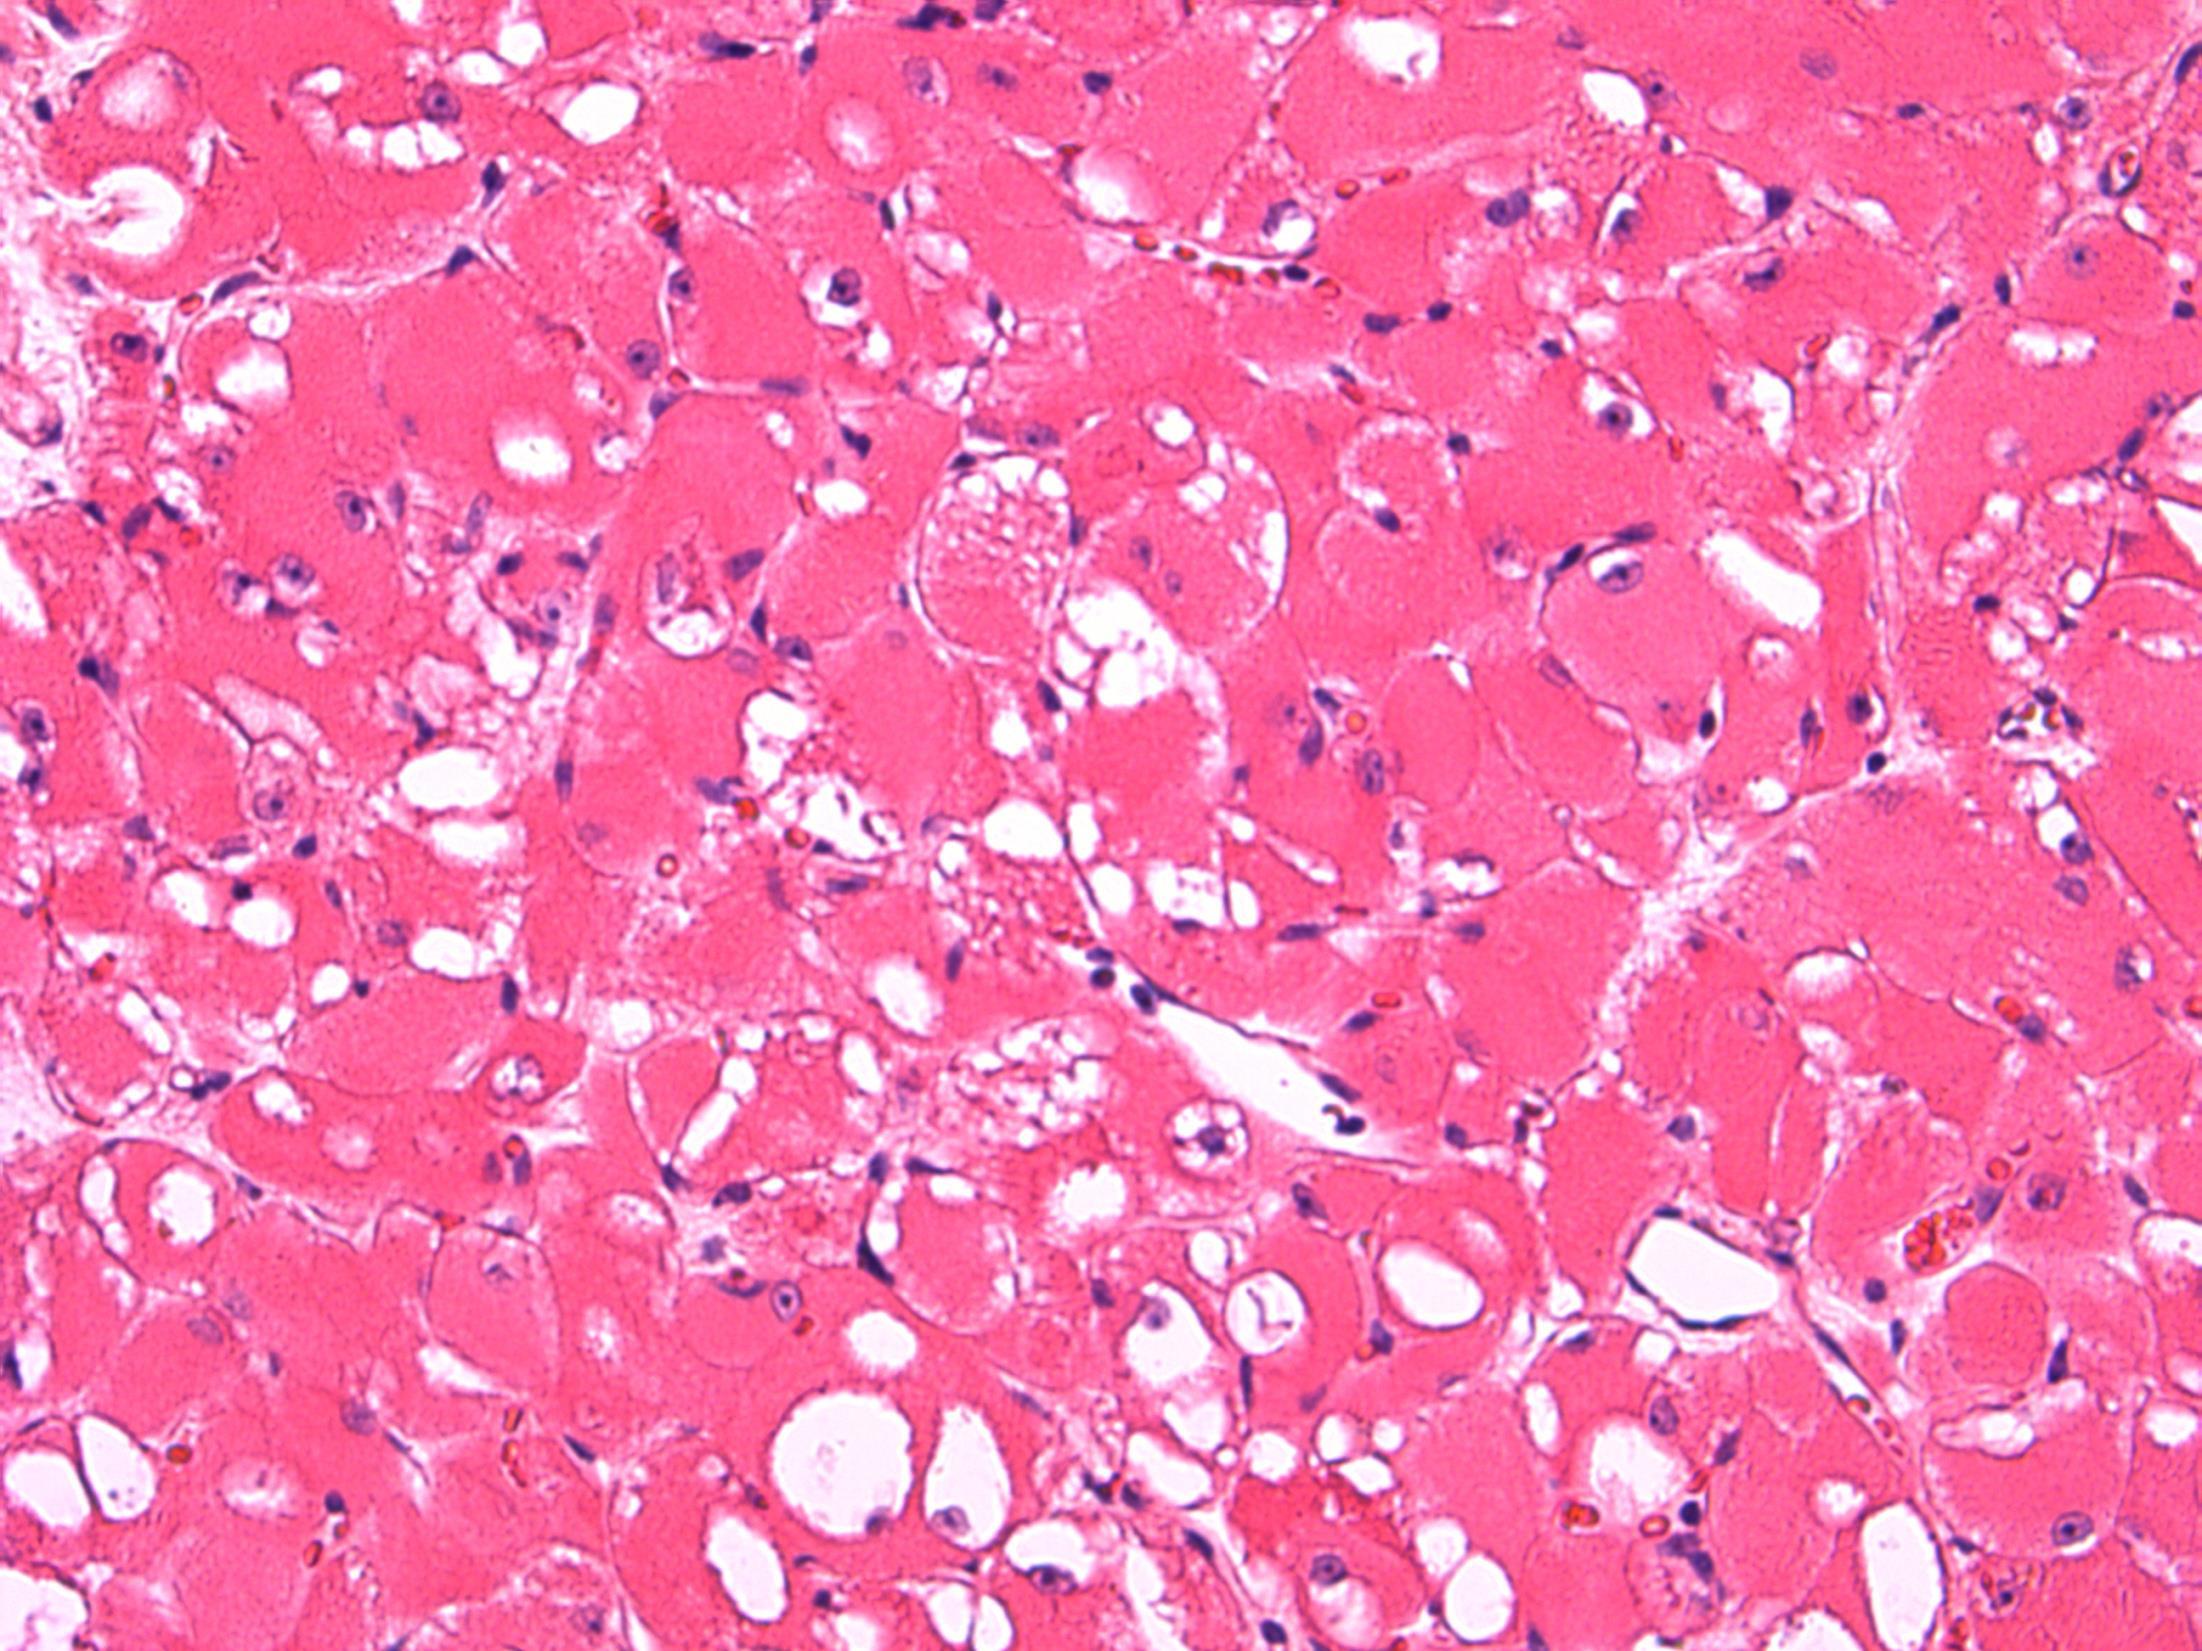

tumour Description: Well cirumscribed tumour with glandular/vascular type structures with vacuolated cytoplasm within fibro-muscular stroma, reactive lymphoid aggregates at periphery. No mitoses, no necrosis. Diagnosis: Adenomatoid tumour Plan: IHC: mesothelial markers calretinin+ AE1/3+ Comments: • Most common paratesticular neoplasm, including epididymis, like in this case • Mesothelial in origin; benign • Wide spectrum of growth patterns – tubular, solid, cystic, angiomatoid • Differential Diagnosis : – Adenocarcinoma (BerEp4/ MOC31+) – Malignant mesothelioma (necrosis/ mitoses/ more infiltrative)

Adenomatoid